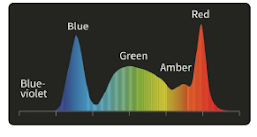

Технология многоспектрального композитного формирования изображения:

5 независимо управляемых высокоточных светодиодов обеспечивают работу специальных световых режимов для решения различных клинических задач в процессе диагностики и лечения.

Специальные оптические режимы:

Визуализация с улучшением текстуры и цвета (TEI)

Визуализация с улучшением текстуры и цвета (TEI)

Выделение текстуры изображения для облегчения выявления новообразований.

Улучшенная визуализация гемоглобина (HEI)

Улучшенная визуализация гемоглобина (HEI)

Выявление глубоких сосудов, контроль источников кровотечения.

Двухцветная визуализация (DSI)

Двухцветная визуализация (DSI)

Выявление и классификация опухолевых образований, прогнозирование глубины инфильтрации.

Спектральная визуализация цветовой палитры (PSI)

Спектральная визуализация цветовой палитры (PSI)

Определение степени воспаления и атрофии, повышение вероятности обнаружения рака на ранних стадиях.